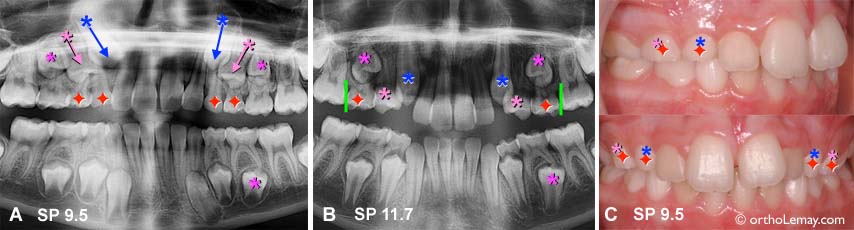

Cas SP : (A) À l’âge de 9.5 ans, la radiographie montre que la direction d’éruption des canines et premières prémolaires supérieures est déjà inclinée vers l’avant, particulièrement du côté droit. Des extractions sélectives sont alors proposées pour tenter d’influencer la direction d’éruption. (B) Une radiographie panoramique prise 2 ans plus tard montre comment les canines et les prémolaires on changé leur direction d’éruption. Les canines sont maintenant presque verticales. Les premières prémolaires font éruption. À ce stage, il est indiqué d’extraire les deuxièmes molaires temporaires supérieures ET de poser un mainteneur d’espace pour éviter la migration des molaires (lignes vertes) en attendant l’éruption des autres dents. (C) Photos cliniques correspondant à la radiographie en (A) et indiquant quelles dents temporaires seront extraites.

L’arcade inférieure est gardée sous observation mais il sera éventuellement indiqué d’extraire la molaire temporaire au dessus de la 2ième prémolaire inférieure gauche (*) qui penche vers l’arrière et ne résorbera pas les deux racines également. (Voir la légende pour identifier les dents)

À noter que, comme dans la plupart des cas d’extractions sélectives, bien que l’éruption soit améliorée, il manque toujours d’espace et des corrections orthodontiques seront tout de même indiquées lorsque l’éruption des dents sera complétée.